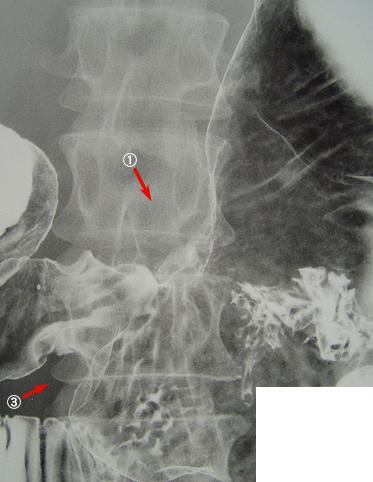

疾病(病理主体)的分类恶性上皮性肿瘤/印戒细胞癌

部位(按器官分)胃(部位)/2个以上

检查方法X线

肿瘤的肉眼分类3型(溃疡浸润型)/

肿瘤最大直径40以上

肿瘤的深度s(a)